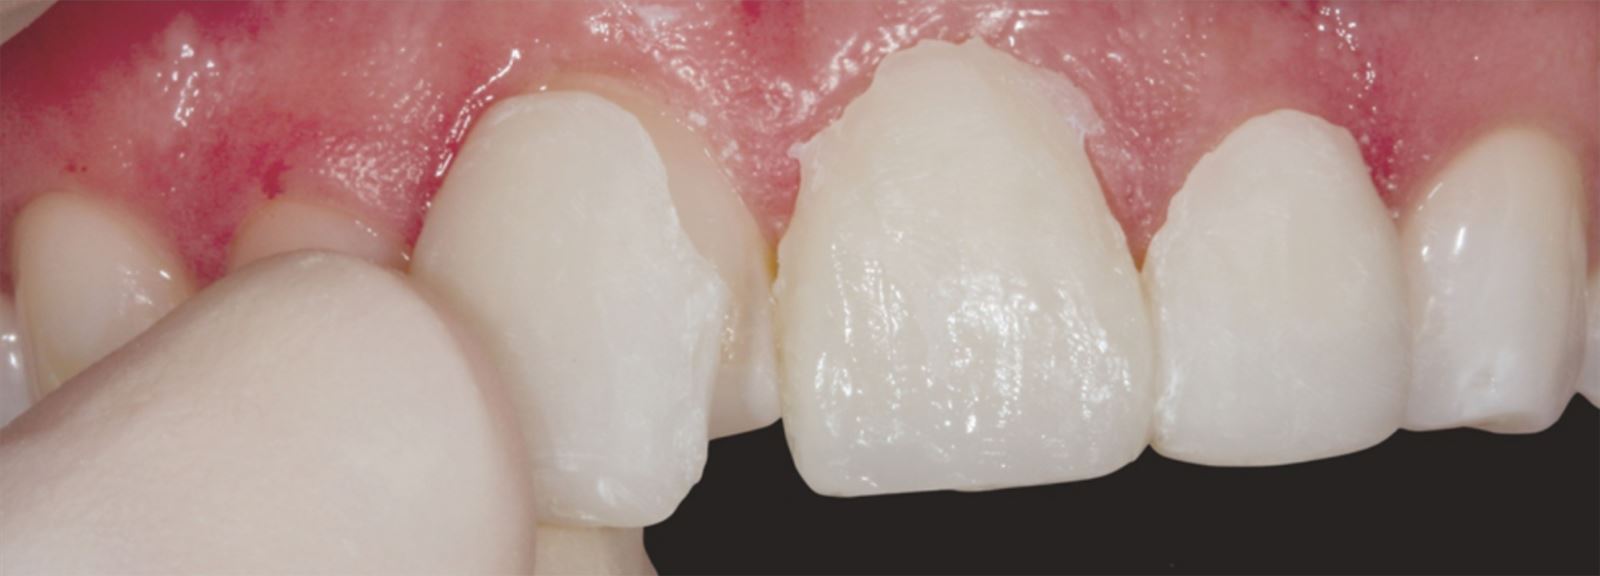

Mladá žena ve věku kolem 20 let, kterou trápila diskolorace horních frontálních zubů po dřívějším traumatu, vyhledala ošetření u Dr. Jaleeny Fischer-Jessop, DDS, MBA. Hledala řešení, které by obnovilo její úsměv. Pacientka byla ošetřena konzervativní a cenově dostupnou metodou: kompozitními fazetami bez preparace, přímým bondingem. Dr. Fischer-Jessop zvolila tento postup k překrytí diskolorace a sjednocení horních zubů s dolními frontálními – bez nutnosti invazivnějších výkonů, jako jsou implantáty, nebo nákladných laboratorně zhotovovaných fazet. Pro zesvětlení zubů byly vybrány odstíny B1D a Enamel White (EW) a odstín Universal Body (UB) kompozitu Transcend™ byl použit k přirozenému splynutí okraje v cervikálních oblastech.

Pacientka ve 20 letech s anamnézou traumatu horních frontálních zubů. Přestože trauma proběhlo, zuby zůstaly stabilní, takže implantáty nebyly nutné.

Pacientka měla výrazné estetické obavy a současně byla finančně limitována. S ohledem na tyto okolnosti byly zvoleny kompozitní fazety bez preparace jako vhodné řešení.

Aplikace kompozitu:

Kompozit Transcend v odstínu B1D byl aplikován od dvou třetin výšky korunky od incisální hrany směrem k cervikální oblasti, kde se postupně ztenčoval. Odstín Universal Body (UB) byl nanesen v cervikálním třetině, závěrečné vrstvy tvořil Enamel White (EW) a malé množství UB v marginální oblasti pro přirozené splynutí.